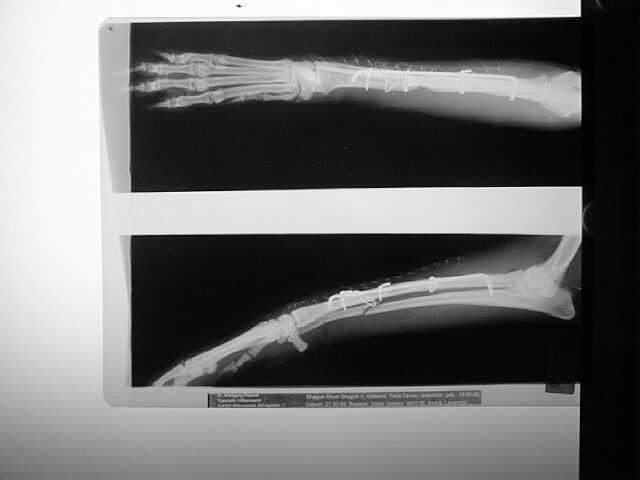

Elle-Speichen-Fraktur

paraossäre Klammer-Cerclage-Stabilisierung